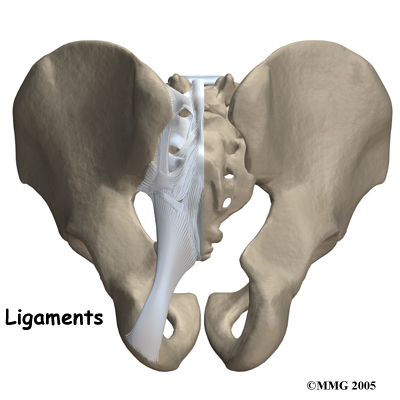

The SI joint is held together by several large, very strong . The strongest ligaments are in the back of the joint outside of the pelvis. Because the pelvis is a ring, these ligaments work somewhat like the hoops that hold a barrel together. If these ligaments are torn, the pelvis can become unstable. This sometimes happens when a fracture of the pelvis occurs and the ligaments are damaged. Generally, these ligaments are so strong that they are not completely torn with the usual injury to the SI joint.

Injury to the SI joint is thought to be a common cause of pain. Injury can occur during an automobile accident. One common pattern of injury occurs when the driver of a vehicle places one foot on the brake before a collision. The through the foot on the brake is transmitted to the pelvis causing a twisting motion to this side of the pelvis. This can injure the SI joint on that side resulting in pain. A similar mechanism occurs with a fall on one buttock. The force again causes a twisting motion to the pelvis and may injure the ligaments around the joint.